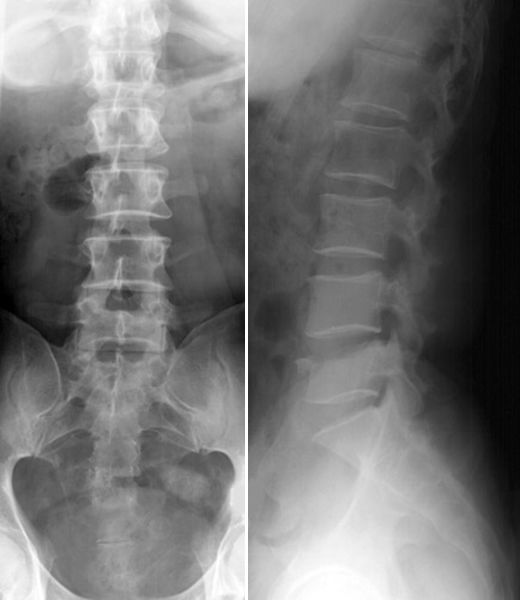

正常腰椎

疼痛科怎么理疗疼痛科医生、康复理疗科医生、针刀针灸医生应掌握的常见骨科疾病X光片_https://www.jmylbn.com_新闻资讯_第57张

L5腰椎骨折

疼痛科怎么理疗疼痛科医生、康复理疗科医生、针刀针灸医生应掌握的常见骨科疾病X光片_https://www.jmylbn.com_新闻资讯_第58张